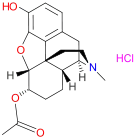

6-Acetyldihydromorphine hydrochloride 6-Acetyldihydromorphine hydrochloride |